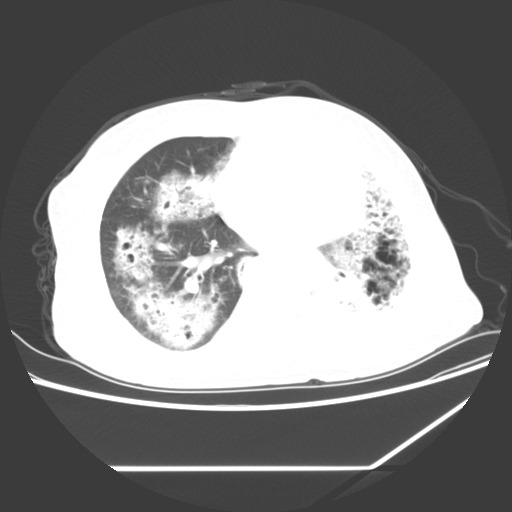

标题: CT25393:病人45岁,咳嗽,吐黄痰带血丝,发热,胸闷月余 [打印本页]

标题: CT25393:病人45岁,咳嗽,吐黄痰带血丝,发热,胸闷月余

1、左肺中央型肺癌并双肺弥漫性转移   2、双肺部感染    3、肺大泡     4、左侧胸腔积液

双侧肺弥漫性病变,可见“空泡征”及“蜂窝征”,考虑肺泡癌可能性大,左侧胸腔积液,考虑胸膜受累可能!

考虑肺泡癌,建议排除感染。

考虑肺泡癌

1)不排除肺泡癌可能。2)左侧胸腔积液。